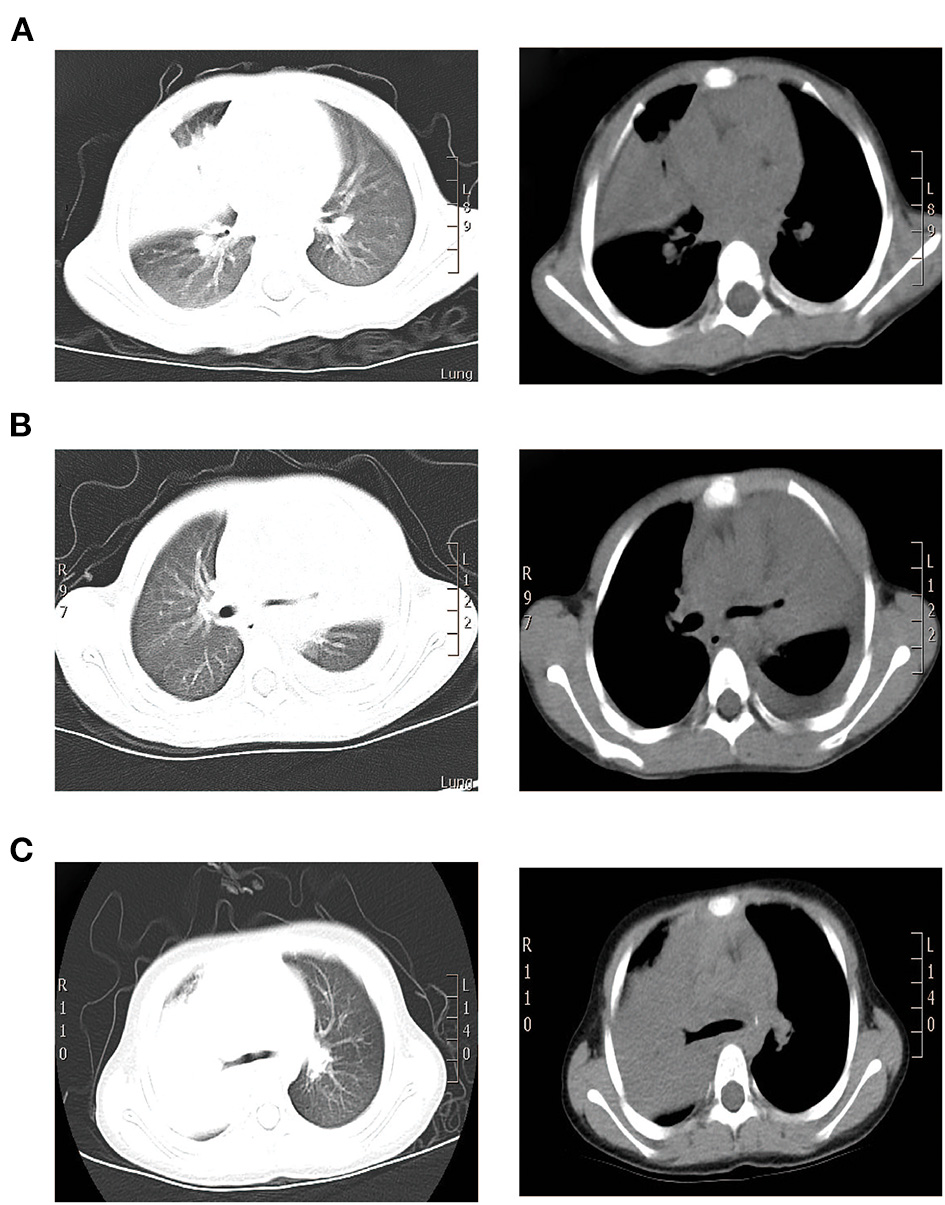

A 1.9-year-old girl was referred to our hospital on March, 2016 due to 4-day fever and cough, with no pertinent past medical history. Physical examination revealed temperature 37.4°C, heart rate 120 beats/min, respiration 50 times/min, blood pressure 90/60 mm Hg, and transcutaneous oxygen saturation 92% without oxygen administration, fatigue, and depressions in suprasternal fossa, supraclavicular fossa, and intercostal space. She developed hypoxemia, so the reservoir mask of 6 l/min was utilized for ventilatory support. The right lung showed diminished breath sounds. Cardiovascular, nervous system, extremities, antinuclear antibodies (ANAs), and extractable nuclear antigens (ENAs) examinations were normal. Routine blood tests showed the following results: hemoglobin (Hb) 118 g/l, white blood cell (WBC) 7.83 × 109/L, neutrophils (N) 53.3%, lymphocytes (L) 40.4%, and C-reactive protein (CRP) 156 mg/l. Arterial blood gas analysis revealed a pH of 7.48, partial pressure of carbon dioxide in artery (PaCO2) of 42 mm Hg, partial pressure of oxygen in artery (PaO2) of 50 mm Hg, base excess (BE) of 6.9 mmol/l, and oxygenation index of 238. Pulmonary CT suggested consolidation with atelectasis in the middle lobe of right lung (Figure 1A).

Figure 1

CT scan findings of three cases. (A) Pulmonary CT results of case 1 suggested consolidation with atelectasis in the middle lobe of right lung. (B) Pulmonary CT of case 2 suggested inflammatory consolidation in the upper and middle lobes of left lung with left pleural effusion. (C) Pulmonary CT of case 3 suggested substantial pulmonary consolidation in the upper and middle lobes of right lung accompanied by significant effusion (Left: lung window image; Right: mediastinal window image).

A 2.4-year-old girl was hospitalized on October, 2015 due to 3-day persistent fever and cough, without underlying disease. Reservoir mask of 10 l/min was utilized for ventilatory support. Due to pulmonary CT suggested inflammatory consolidation with atelectasis, the first FB was used for treatment and etiological diagnosis. After 2 days of cephalothin and azithromycin treatment, she still had fever and cough and developed hypoxemia. Arterial blood gas revealed a pH of 7.44, PaCO2 of 45 mm Hg, PaO2 of 52 mm Hg, and oxygenation index of 247. Then, nasal high-flow oxygen of 10 l/min was adopted and methylprednisolone was applied for anti-inflammation. Physical examination revealed temperature 38.3°C, heart rate 135 beats/min, respiration 45 times/min, blood pressure 85/50 mm Hg, transcutaneous oxygen saturation 93% without oxygen administration, fatigue, flaring of nares, and decreased respiratory sound in the left lung. Cardiovascular, nervous system, extremities, ANA, and ENA examinations were normal. The routine blood tests indicated Hb 118 g/l, WBC 6.25 × 109/L, N 55.3%, L 37.6%, and CRP 26 mg/l. On day 4, pulmonary CT suggested inflammatory consolidation accompanied with left pleural effusion (Figure 1B).

On the 2nd day, pulmonary CT suggested substantial pulmonary consolidation in the upper and middle lobes of the right lung accompanied by significant effusion (Figure 1C). Due to persistent fever and significant elevation on blood inflammatory indicators, an additional methylprednisolone of 10 mg/kg/d was added for anti-inflammation and it was applied for 14 days. B-ultrasound showed that the maximum depth of pleural effusion was about 70 mm. Then, thoracentesis was performed and 300 ml of light yellow liquid was drained. Due to plastic casts in the airway and persistent consolidations in X-ray, FB was performed on the 3rd day and 6th day again. His temperature returned to normal and blood oxygen improved on 7th day. On 9th day, B-ultrasound showed no pleural effusion. The chest X-ray was normal and the titer of MP-IgM was increased by eight times on the 14th day. This patient had a fever for a total of 7 days after admission and discharged with azithromycin (oral) on the 15th day (Figure 4). No other etiological evidence was found in body fluid and secretions. She was followed-up without any discomfort on the 22nd and 52nd day.